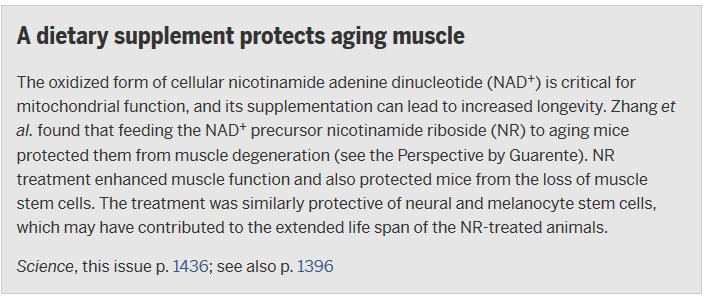

Feeding nicotinamide riboside to aging mice increased their lifespan: ($) http://scim.ag/1WP755I pic.twitter.com/PkSifxF2HF